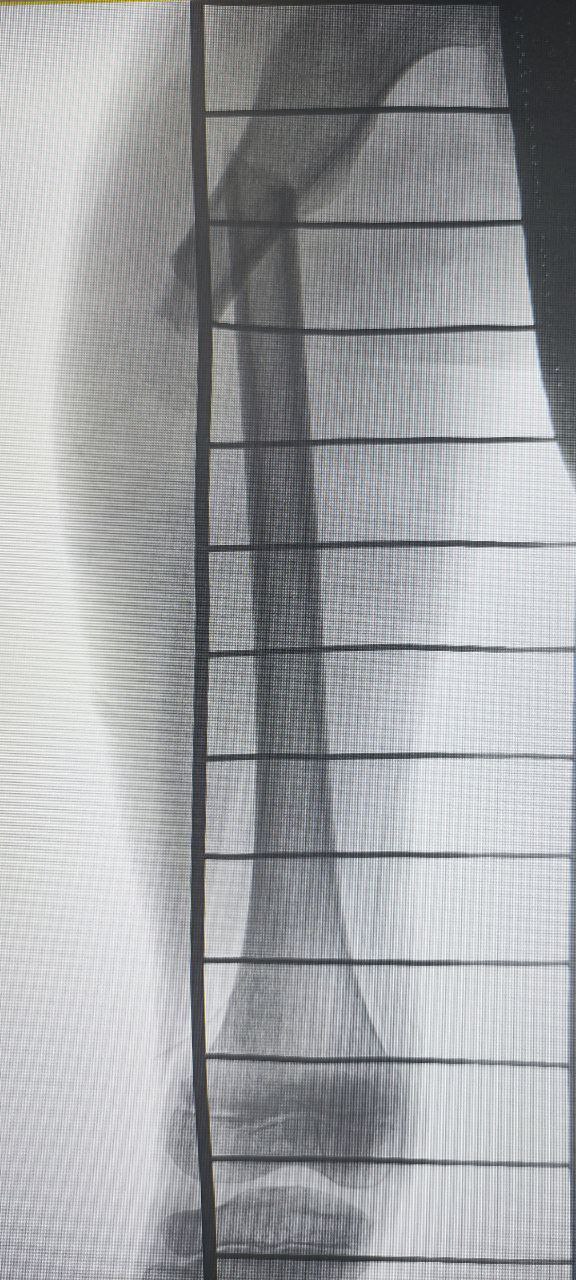

В ДРКБ накануне доставили ребенка с закрытым переломом бедренной кости со смещением. Его экстренно прооперировали, сейчас состояние стабильное.

Врачи отмечают, что травма произошла на необорудованном склоне, где отсутствовали защитные ограждения. На сращение перелома в среднем требуется 5–6 недель, а на реабилитацию – до нескольких месяцев в зависимости от индивидуальных особенностей организма и соблюдения рекомендаций.